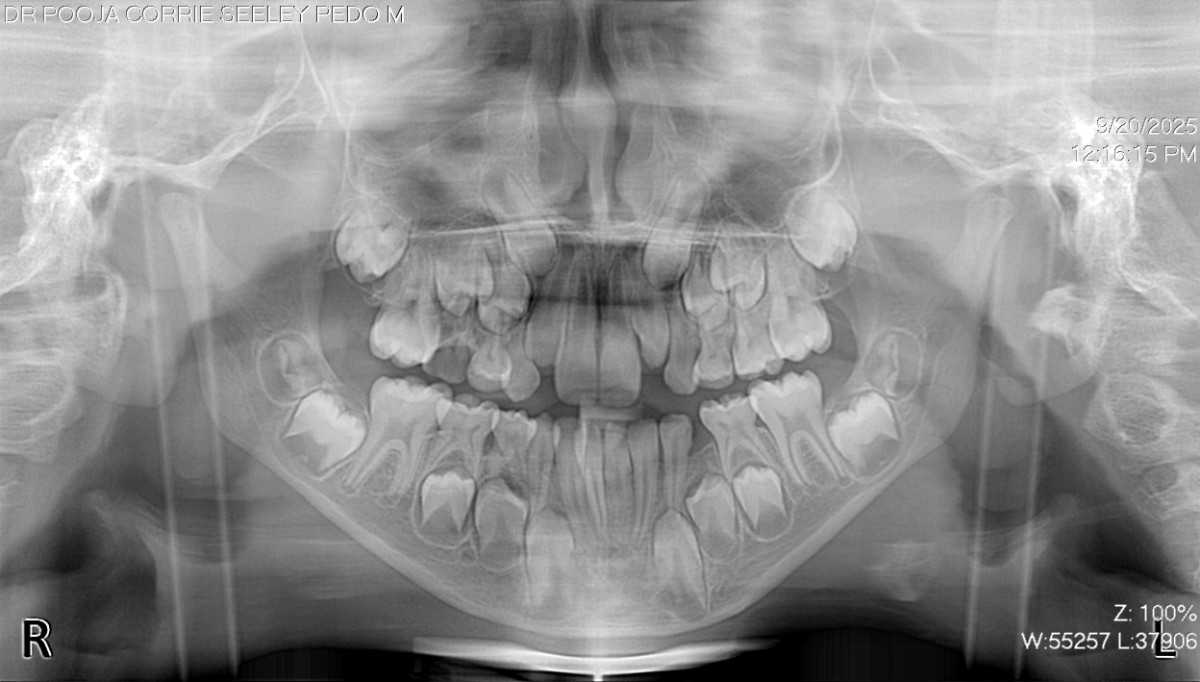

The diagnosis was accurate due to clinical and radiographic examination, & the lower primary molar is prematurely exfoliating. The clinical examination reveals that adjacent teeth have begun to fill the gap. An X-ray deprived of visible space and a 5-year loss potential revealed emerging permanent tooth buds in anticipated sites. Dr. Pooja was treated using a designed lingual holding arch with U-loops. The device helps to stabilize the molars to allow the adjustment to various mandible development. The parents were thoroughly informed about the process, benefits, and care needs were clarified.

The patient was a healthy six-year-old, male child, with no severe health issues. The lower primary molar fell out early because it was decaying. The parents saw that the teeth adjacent to the child's mouth had moved during a normal dental exam. The child was helpful during the diagnosis and treatment procedure. Early intervention through preventive orthodontics was sought to avoid more complex orthodontic issues & maintain a healthy developing smile.